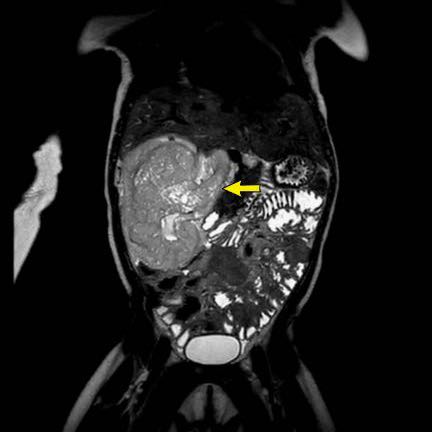

Hình ảnh chuỗi xung T2W mặt phẳng coronal cho thấy một khối u không đồng nhất ở thận trái với các thành phần nang nhỏ.

Khối u ngấm thuốc kém hơn so với phần nhu mô thận bình thường còn lại ở ngoại vi.

Các thành phần đặc của khối u cho thấy hạn chế khuếch tán rõ rệt (mũi tên).

Đây là u Wilms ở bé trai năm tuổi. Hóa trị tiền phẫu được thực hiện theo phác đồ Umbrella của SIOP-RTSG, sau đó tiến hành cắt thận.